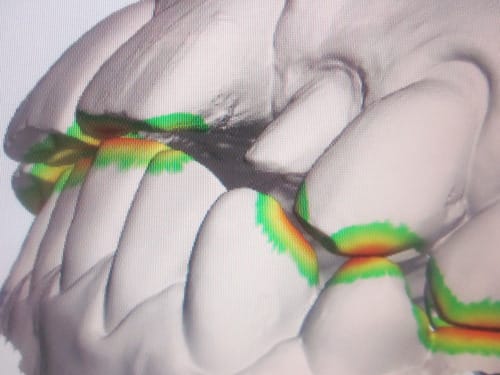

J'ai le plaisir de vous présenter un cas clinique de couronne E-Max sur 22 réalisé à partir de l'empreinte optique intra-buccale.

j'attends encore quelques photos de la CAO de leur part pour mettre à jour l'article mais je voulais déjà vous faire profiter de "ma partie"...